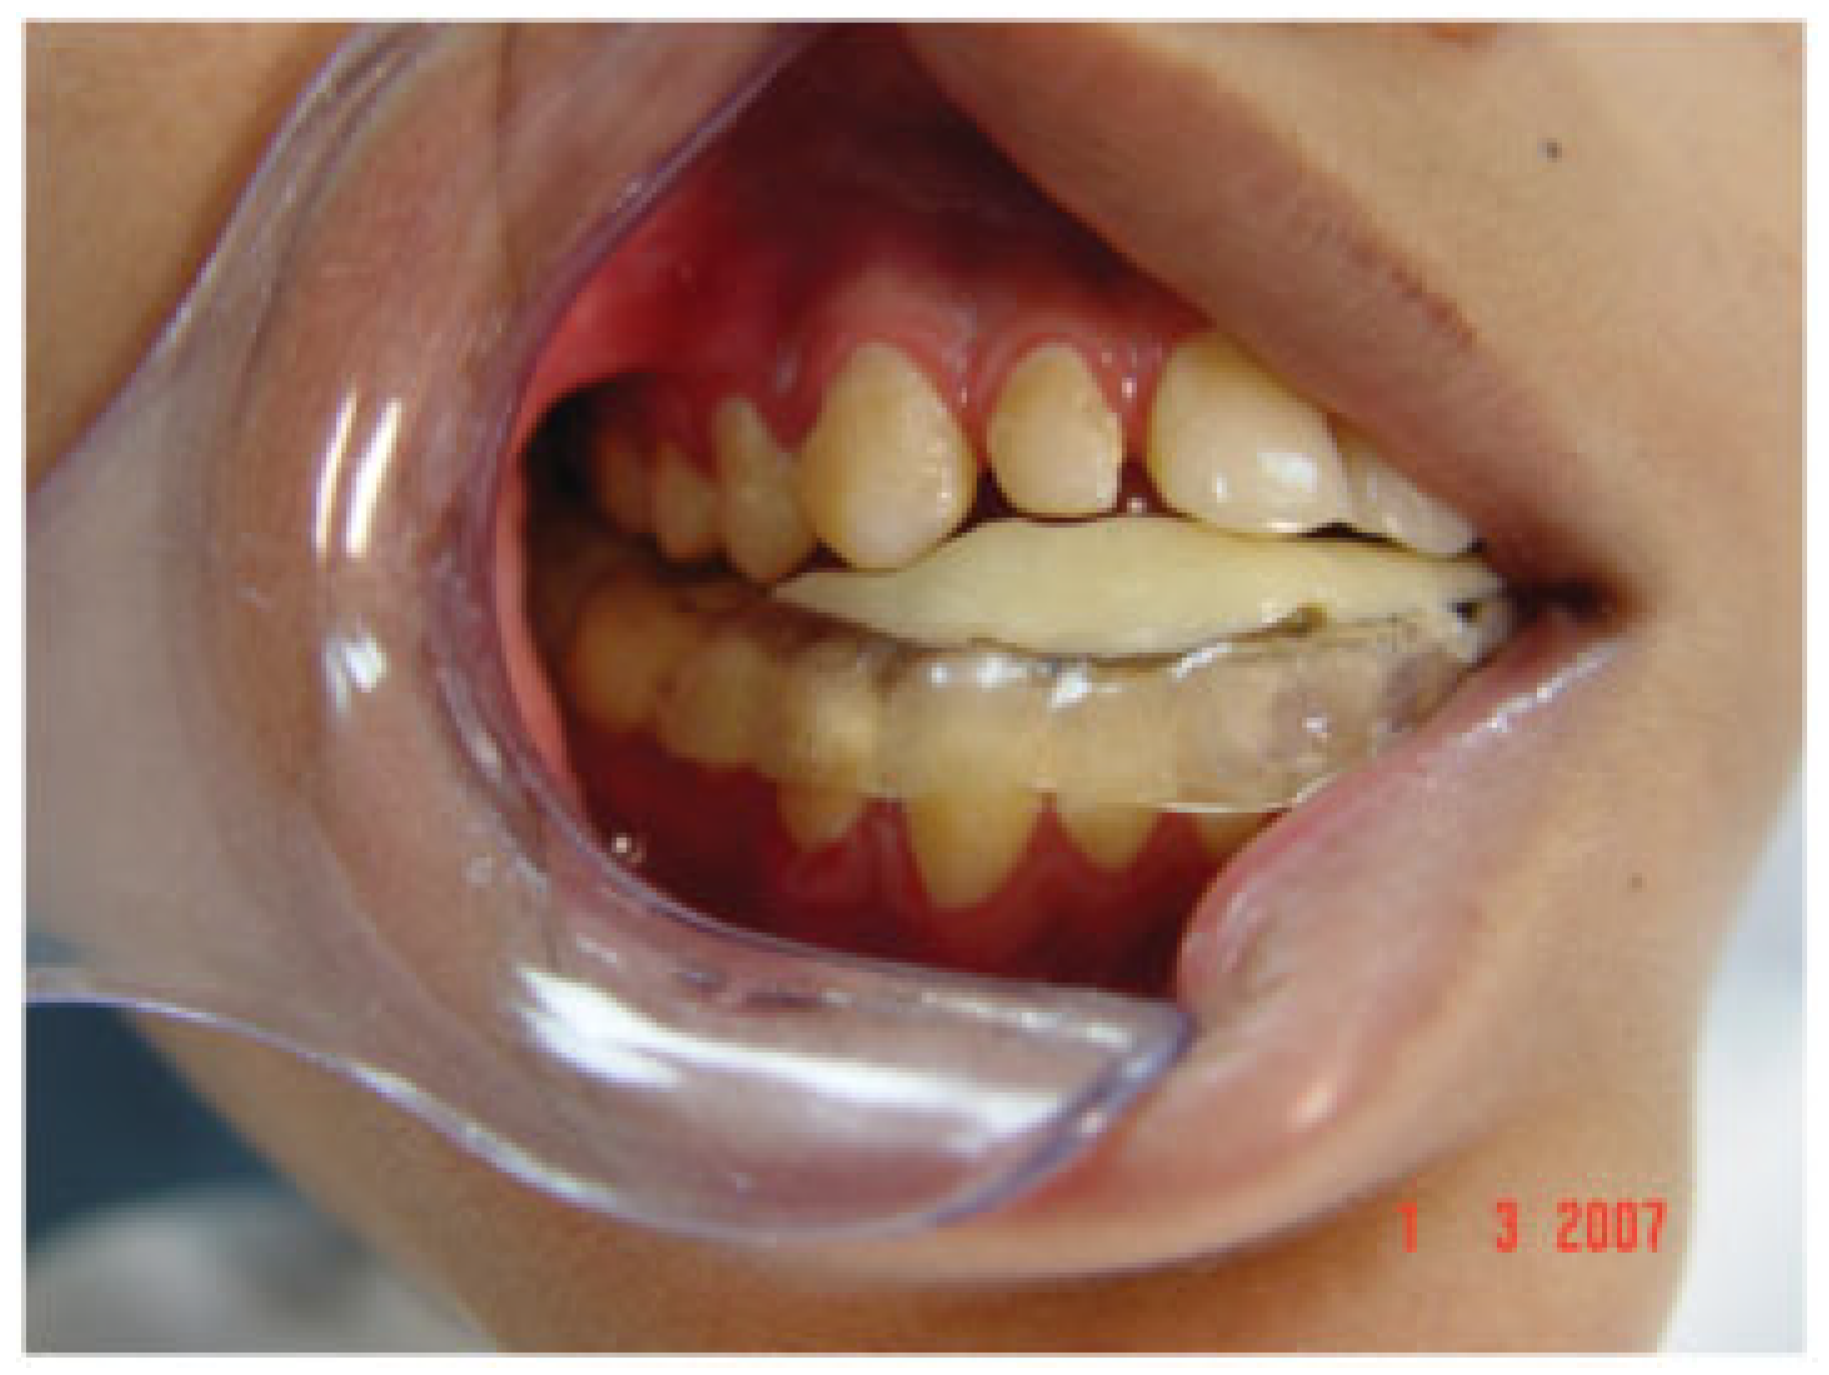

Figure 15. An acrylic plate was used to facilitate closure of the open bite. To achieve gradual closure of the open bite, the plate is trimmed in those areas that require the maxillary teeth to passively erupt.

At the conclusion of distraction, the patient had an open bite on the right side (Figure 14), which was gradually closed by encouraging passive eruption of the maxillary dentoalveolar segment through the selective grinding of the occlusal surfaces of a removable denture (Figure 15). Not only had mandibular distraction reduced his asymmetry, (Figure 16) but it had also corrected the deviation of his mandible on mouth opening (Figure 17). There was no limitation in mandibular movement in right and left lateral excursion (sideway movements) and protrusion. Before the open bite could be completely closed the patient was lost to follow-up.